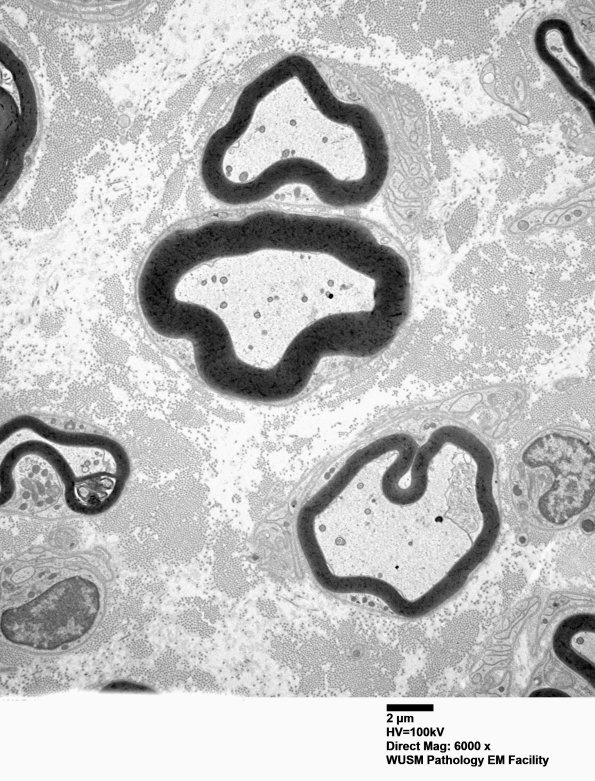

There is little to identify these axons as regenerated other than “thinned-myelin-for-axon-caliber”. (electron micrographs)